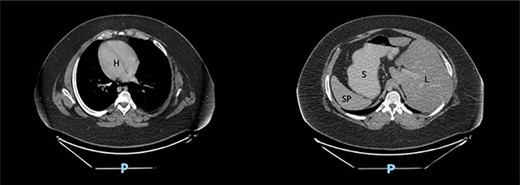

We present the case of a 19-year-old male patient with a known preoperative diagnosis of SIT, which was discovered in childhood after diagnosis of a pleural effusion treated by placing a chest tube for drainage (Figs 1 and 2). The patient weighed 156 kg and was 177 cm tall, with a preoperative body mass index (BMI) of 49.8 kg/m2, without chronic-degenerative comorbidities. The patient failed to achieve weight loss despite multiple attempts at diet and exercise therapy. After performing a detailed preoperative evaluation, it was proposed to perform an Roux-en-Y laparoscopic gastric bypass (RYGB) for definitive weight loss. The patient is admitted to the operating room to perform the procedure with minimal adjustments in terms of surgical technique. The procedure is performed with the mirror technique from the conventional manner due to the patient’s baseline conditions (Fig. 3). Given the complexity of the case, the surgery was performed for a longer period of time with a total surgical time of 150 min. The patient was subsequently transferred to the recovery room without complications in the immediate or mediate post-operative period.

Computed tomography scan of the abdomen in our patient with SIT showing dextrocardia (H), spleen (SP) and stomach (S) located on the right side and liver (L) on the left side.